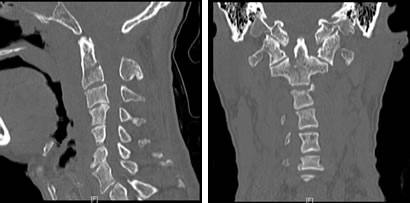

4月24日晚,48岁的王先生因外伤致头颈部疼痛1个多小时,于23点收入我院闽南医院神经外科。经检查,其被诊断为:1.右额、颞部硬膜外血肿;2.右额骨、右颞骨、右蝶骨骨折、右颧骨骨折;3.颈1、2、3骨折脱位,寰椎后弓大部先天缺失。在医护人员的积极治疗下,病人颅脑出血得到控制,于4月25日转入骨科继续治疗。

针对王先生的病情,骨科主任陈飞博士组织全科进行大讨论,认为病人系高位颈椎多发损伤,合并先天性寰椎后弓大部缺失畸形、寰枢椎半脱位,随时有全身瘫痪和死亡的危险,这类病人在省属三甲医院都并非常见。精心讨论后,治疗组决定先行颅骨牵引,进行颈椎复位,待全身情况稳定后行高位颈椎内固定融合术。

上颈椎的解剖结构非常复杂,周围有众多的主要神经、血管,手术操作时稍有不慎,就可能招致灾难性的后果,加上患者寰椎后弓的发育不全,造成延髓处骨性屏障缺失,以及显露、置钉时的解剖标志丧失,极大地增加了手术的难度以及风险。为保障安全,医院根据患者高精度CT三维扫描的原始数据,依托院外高新科技3D打印实验室,制作出1:1的上颈椎模型,真实还原了患者上颈椎骨折及畸形的情况。根据3D打印模型,骨科团队在陈飞博士的主持下进行多次的模拟手术,在毫米级别上,精确地定位了内固定物的置入点、明确了螺钉的方向、直径和长度,并对手术中可能出现的意外作了充分的估计和预演。